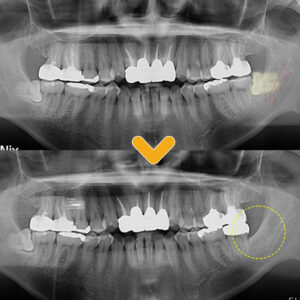

수암동치과 누워있는 사랑니 방치하면 더 큰 문제로 안녕하세요. 모든 진료에 진심을 다하는 곳, 더플러스치과입니다. ​ 우리의 입안에서 갑자기 찾아오는 불청객인 사랑니는 예고 없이 찾아오곤 합니다. 입안의 가장 안쪽에서 자라 나오는 사랑니의 특성상 칫솔이 잘 닿지 않는 곳에 위치하여 구강 위생관리를 꼼꼼히 하기에 여간 어려운 일이 아닌데요. ​ 평소에 식사 시에 더보기…